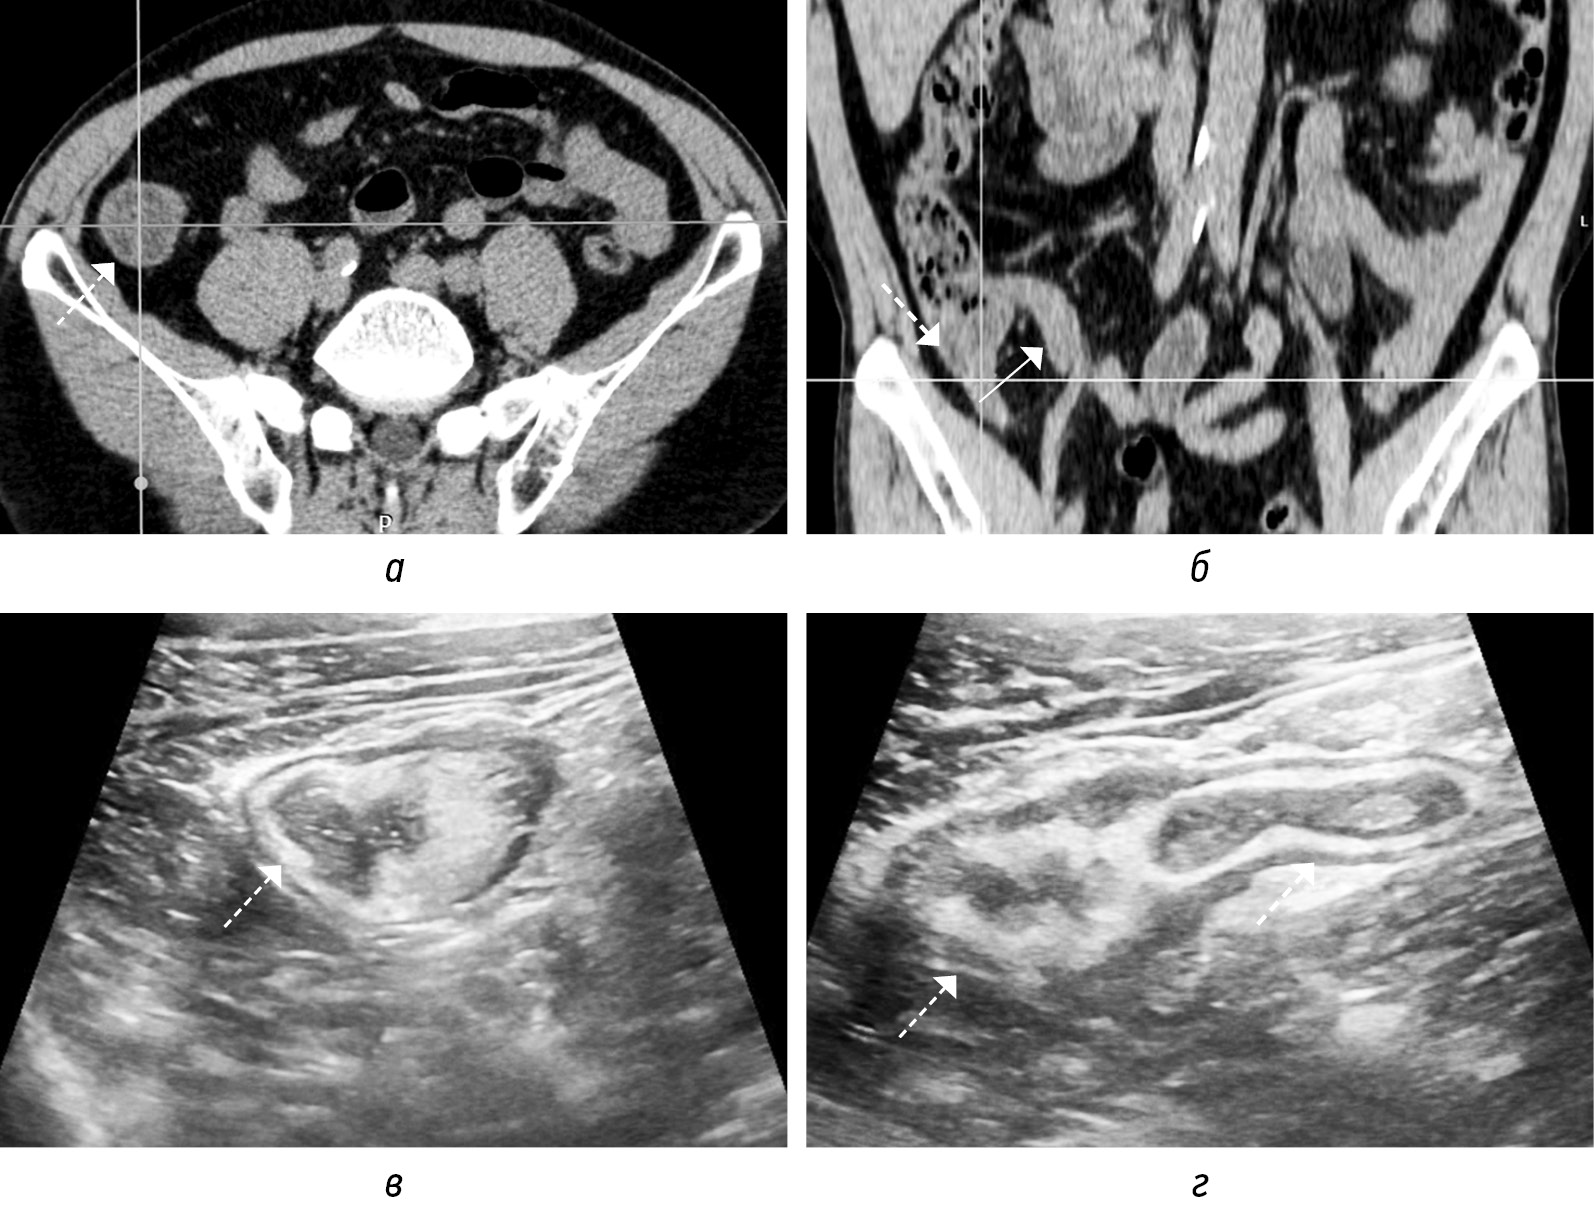

Рис. 9. На нативных КТ-томограммах в аксиальной (а) и фронтальной (б) плоскостях и соответствующих сонограммах (в, г) визуализируется аппендикс (стенки толщиной 4 мм, в просвете (до 6 мм) неоднородное содержимое) (стрелка) с отеком стенок слепой кишки (пунктирная стрелка). Прилежащая жировая клетчатка без видимых изменений

Fig. 9. On native CT-tomograms in the axial (а) and frontal (б) planes and corresponding sonograms (в, г), the appendix is visualized (walls 4 mm thick, in the lumen (up to 6 mm) heterogeneous contents) (arrow) with edema of the walls of the cecum (dotted arrow). Adjacent adipose tissue without visible changes

Просвет аппендикса может расширяться за счет неоднородного внутреннего содержимого без наличия (рис. 6, а, г) или с присутствием (рис. 6, б, в, д, е) аппендиколита. Другие косвенные признаки ОА: отек периаппендикулярной жировой клетчатки (рис. 7, а, б; 8, а, б); утолщение за счет отека прилежащей стенки кишки (рис. 9, а–г); расширение просвета кишки за счет газа иди жидкости с ослабленной перистальтикой; периаппендикулярное жидкостное скопление или абсцесс (рис. 10, а, б); лимфоаденопатия (рис. 11, а); абдоминальный выпот (рис. 11, г) [3, 16, 18].

Осложненный ОА характеризуется либо перфорацией (тип 3), либо ожидаемой перфорацией (тип 2). Ключевым визуализационным признаком осложненного ОА являются выраженные изменения периаппендикулярной ткани: гиперэхогенность на УЗИ или тяжистое уплотнение на КТ. Выраженная, но все еще локализованная периаппендикулярная жидкость или обструкция наблюдается при тяжелом флегмонозном ОА (тип 2а). Гангренозный ОА (тип 2б) характеризуется наличием интрамурального газа и/или потерей эхогенного подслизистого слоя. Некоторые авторы классифицируют тяжелый флегмонозный ОА (тип 2а) и даже гангренозный ОА (тип 2б) как неосложненный ОА, предположительно потому, что они определяют осложнения исключительно по наличию перфорации. Нoffmann J.C. et al. предлагают классифицировать эти типы как осложненные ОА в соответствии с консенсусным заявлением Европейской ассоциации эндоскопической хирургии, опираясь на многочисленные исследования, показавших, что аппендиколит с обструкцией (рис. 15, а–г), выраженное периаппендикулярное воспаление и гангрена указывают на неизбежную перфорацию [2]. Перфорация может быть прикрытой с абсцессом (тип 3а) или неприкрытой со свободной жидкостью, газом и гноем в брюшной полости (тип 3б). Иногда можно обнаружить псевдообразование аппендикса за счет вовлечения в воспалительный процесс прилежащих петлей тонкой или толстой кишки, что также представляет собой локализованную форму перфорации, т. е. тип 3а.

Рис. 15. КТ-томограммы (а) в трех плоскостях на уровне аппендикса с наличием в нижней трети аппендиколита (на изображениях соответствует точке пересечения секущих линий) с обструкцией просвета и расширением просвета выше препятствия, с отеком периаппендикулярной жировой клетчатки. Сонограммы (б–г) в В-режиме демонстрируют аппендиколит, участки аппендикса без расширения просвета и мешковидное расширение выше препятствия (стрелка)

Fig. 15. CT-tomograms (a) in three planes at the level of the appendix with the presence of appendicolitis in the lower third (in the images corresponds to the intersection point of the secant lines) with obstruction of the lumen and expansion of the lumen above the obstacle, with swelling of the periappendicular fatty tissue. Sonograms (б–г) in B-mode demonstrate appendicolitis and areas of the appendix without expansion of the lumen and sac-like expansion above the obstacle (arrow)